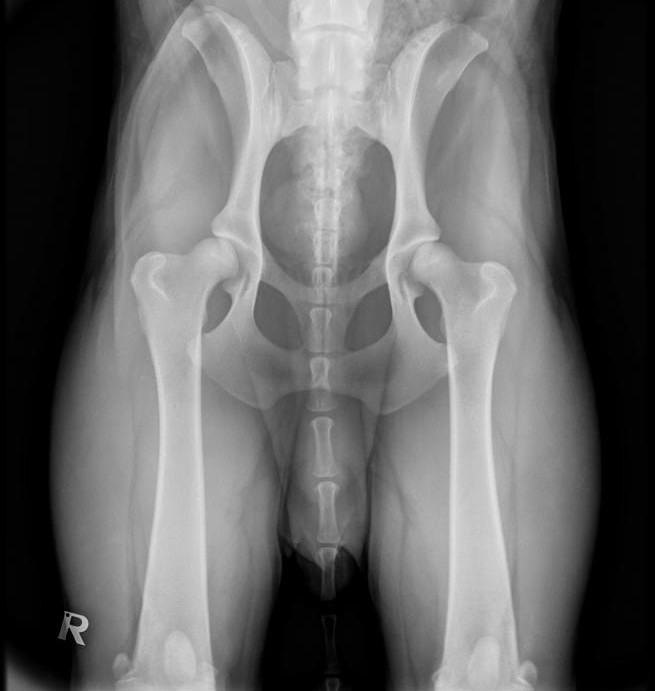

Ist eine bestehende Lahmheit lokalisiert, kann eine Röntgenuntersuchung sinnvoll sein, um das Ausmaß des Schadens zu ermitteln und die richtige Therapie einzuleiten. Frakturen, Luxationen und Bandabrisse sollten chirurgisch versorgt werden. Zerrungen und Prellungen benötigen meist nur Ruhe. Bei tumorverdächtigen Prozessen entscheidet das Biopsie-Ergebnis über das weitere Vorgehen.